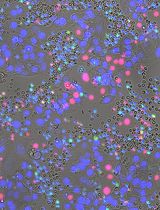

Neovascular diseases of the retina, such as diabetic retinopathy (DR) and age-related macular degeneration (AMD), are proliferative retinopathies involving the growth of new blood vessels on the retina, which in turn causes impairment and potential loss of vision. A drawback of conventional angiogenesis assays is that they are not representative of the angiogenic processes in the retina. In the retina, the new blood vessels grow (from pre-existing blood vessels) and migrate into a non-perfused region of the eye including the inner limiting membrane of the retina and the vitreous, both of which contribute to vision loss. The Matrigel Duplex Assay (MDA) measures the migration of angiogenic capillaries from a primary Matrigel layer to a secondary Matrigel layer, which resembles the pathological angiogenesis in AMD and DR. The methodology of MDA is comprised of two steps. In the first step, the human retinal microvascular endothelial cells (HRMECs) are mixed with phenol red–containing Matrigel (in a 1:1 ratio) and seeded in the center of an 8-well chamber slide. After 24 h, a second layer of phenol red–free Matrigel is overlaid over the first layer. Over the course of the next 24 h, the HRMECs invade from the primary Matrigel layer to the secondary layer. Subsequently, the angiogenic sprouts are visualized by brightfield phase contrast microscopy and quantified by ImageJ software. The present manuscript measures the angiogenesis-inhibitory activity of the Src kinase inhibitor PP2 in primary HRMECs using the MDA. The MDA may be used for multiple applications like screening anti-angiogenic drugs, measuring the pro-angiogenic activity of growth factors, and elucidating signaling pathways underlying retinal angiogenesis in normal and disease states.

The retina consists of organized layers of photoreceptors, interneurons, glia, epithelial cells, and endothelial cells. The proper maintenance of vascular networks is critical to normal visual function [1]. Aberrant angiogenesis is the hallmark of several ocular diseases including age-related macular degeneration (AMD) and diabetic retinopathy (DR) [2]. The angiogenic process in the retina is a complex, multistep process involving endothelial cell invasion, adhesion, chemotactic migration, proliferation, and differentiation into capillary tube–like structures and the production of a basement membrane around the vessel [3]. A survey of literature shows that the Matrigel capillary tube assay is one of the most prevalent angiogenesis assays in cell culture models [4, 5]. In this assay, human microvascular endothelial cells are seeded on a three-dimensional layer of solidified Matrigel (or any other reconstituted basement membrane extracellular matrix). Over a period of 24 h, the cells differentiate into capillary tube–like networks, which can be quantified by digital image analysis. A caveat of this assay is that it does not represent pathological angiogenesis in the eye. The Matrigel assay is more representative of vasculogenesis, which is defined as the differentiation of endothelial cells to yield de novo primitive vascular networks rather than angiogenesis where new capillaries are generated from existing vasculature [6]. Another disadvantage is the lack of a lumen in the capillaries obtained by this assay [7, 8]. Other methods used to measure retinal angiogenesis include the measurement of endothelial cell proliferation or endothelial cell chemotaxis or migration. Although these individual processes are useful indicators of angiogenic activity, they do not provide a holistic representation of the angiogenic cascade [7, 8]. These drawbacks are circumvented by using the Matrigel Duplex Assay (MDA). In the MDA, the angiogenic sprouting (in the secondary Matrigel layer) arises from pre-formed vascular networks in the primary layer [9, 10].